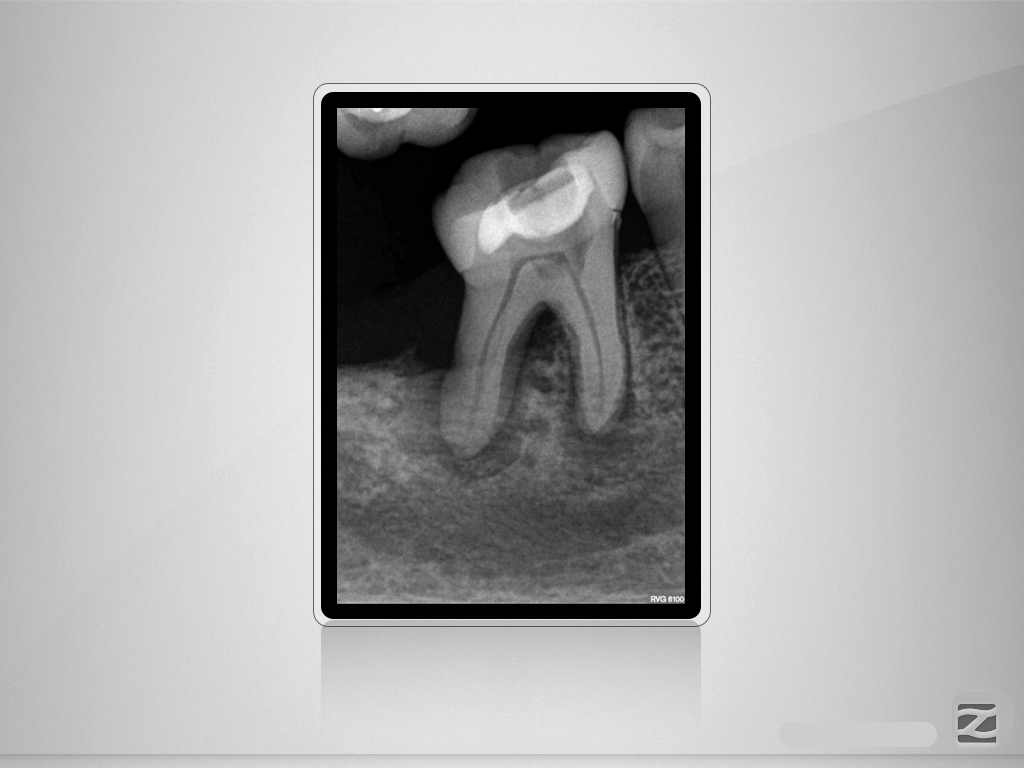

46D.001

Für oder Wider?